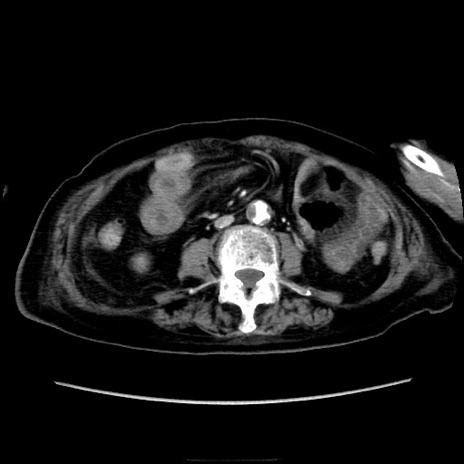

症例40(横断像)

【症例】90歳代女性

【主訴】腹痛・嘔吐

【現病歴】 食欲低下、嘔吐があり昨日他院受診。肺炎と診断され入院となる。入院後より腹部全体に圧痛あり。胃管留置され経過みていたが、症状持続するため、

当院転院となる。

【既往歴】胸椎圧迫骨折、胆石症

【身体所見】腹部:中央に激痛あり、圧痛あり、反跳痛不明

【データ】WBC 17100、CRP 18.82

横断像